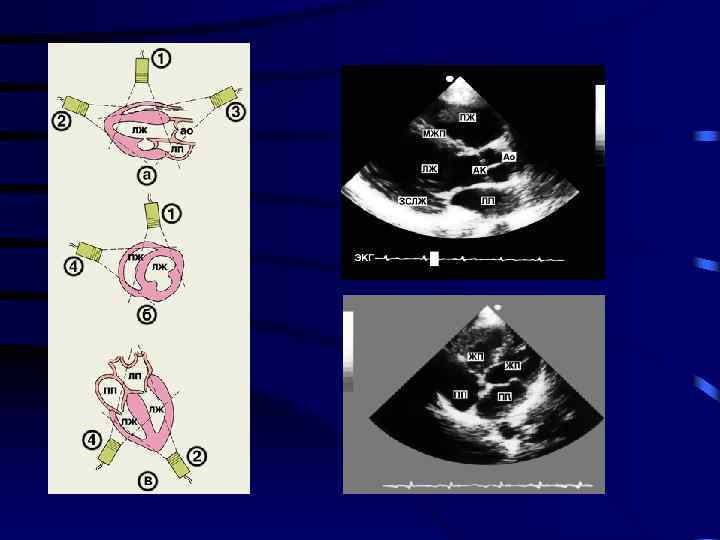

М – метод (от английского motion — движение) Определяют: • толщину стенок, • размеры полостей, • степень раскрытия створок и заслонок клапанов сердца Семиотика увеличение уменьшение изменеиие траектории движения Движение створок митрального клапана в норме

ВС: изменение движения створок клапанов (деформация ) Митральный клапан Аортальный клапан

ВС: гипоэхогенная зона в полости перикарда Сонограмма (Врежим) МС: М-режим ультразвукового исследования гидроперикард